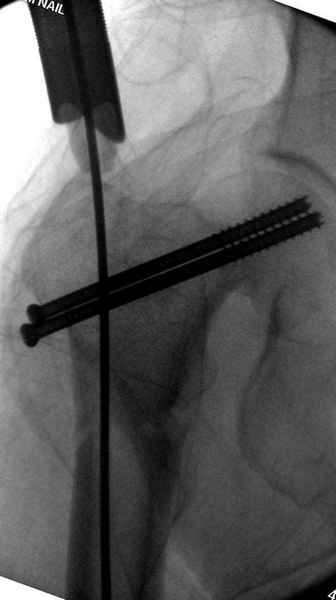

На второй день после выписки упал дома. Снимки приложены. Коллеги рекомендуют удаление шурупа и вытяжение. Что делать?

Привет из солнечного Будапешта с Eurotrauma-2008. Да, замечательный пример. Получается, профилактику расхождения отломков шейки надо было проводить каким-то реконструкционным или проксимальным гвоздем, причем сразу длинной версией. Сейчас, наверно, так и надо бы сделать.

Убрать винты, каким-то джойстиком в вертельной области сделать репозицию шейки, фиксировать ее спицами, а дальше вправлять и фиксировать как вертельный перелом.

Правильно, ситуация изменилась, как говорят у нас теперь "different animal", надо решать проблему подвертельного перелома. При наличии различных вариантов фиксаторов, включая Страйкер Гамма 3, мы выбрали DePuy Antegrade Trachanteric Nail из-за многовариантности проксимальной фиксации и двойного изгиба. Вводится через вертел под 8 градусным углом, и есть достаточный передний диафизарный изгиб, предупреждающий пенетрацию дистального переднего кортекса.